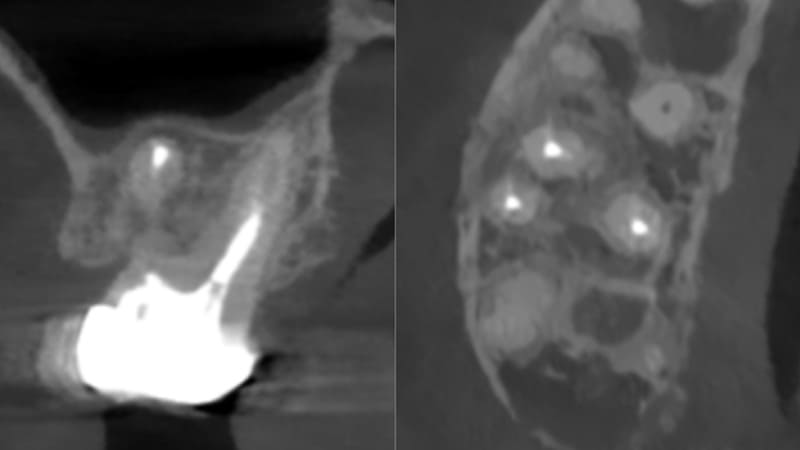

症例①:他院で根管治療していたが膿が止まらないと言われた

| 治療科目 | 根管治療 |

|---|---|

| 主訴 | 他院で根管治療していたが膿が止まらないと言われた。 |

| 治療期間 | 1ヶ月 |

| 治療費 | – |

| 治療内容 | 前歯、根管内をマイクロスコープで確認し汚染部位を除去し根充。 |

| 治療のリスク | 噛み合わせが強い場合歯根破折の可能性あります。まれに再発する可能性があります。その場合外科的歯内治療をするか、抜歯を検討します |